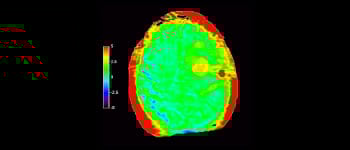

3D APT

Mayor fiabilidad diagnóstica en neurooncología